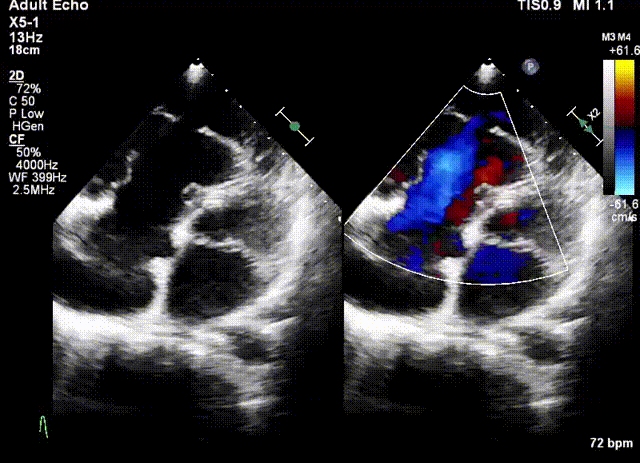

術前超聲